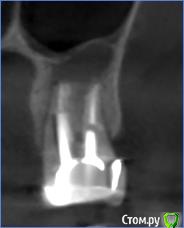

anafree Опубликовано 25 февраля, 2016 Поделиться Опубликовано 25 февраля, 2016 (изменено) Добрый вечер! Подскажите, пожалуйста, возможно ли попробовать перелечить, удалить кисты без удаления зубов? То что дорого, знаю. Интересует, есть ли возможность вообще в данной ситуации. Две верхние семерки, там стоят вкладки и коронки (стоят уже лет 10) и нижняя 7-ка, там пока временная коронка на штифте просто стоит. Ни один из трех зубов не беспокоит. Изменено 25 февраля, 2016 пользователем anafree Ссылка на комментарий

DmitrySH Опубликовано 26 февраля, 2016 Поделиться Опубликовано 26 февраля, 2016 Да, можно спасти, но возможно что не все, для полноценного ответа нужно больше снимков. И то, на снимках всего не видно. Чем качественнее сделаны вкладки, тем сложнее их извлекать. Ссылка на комментарий